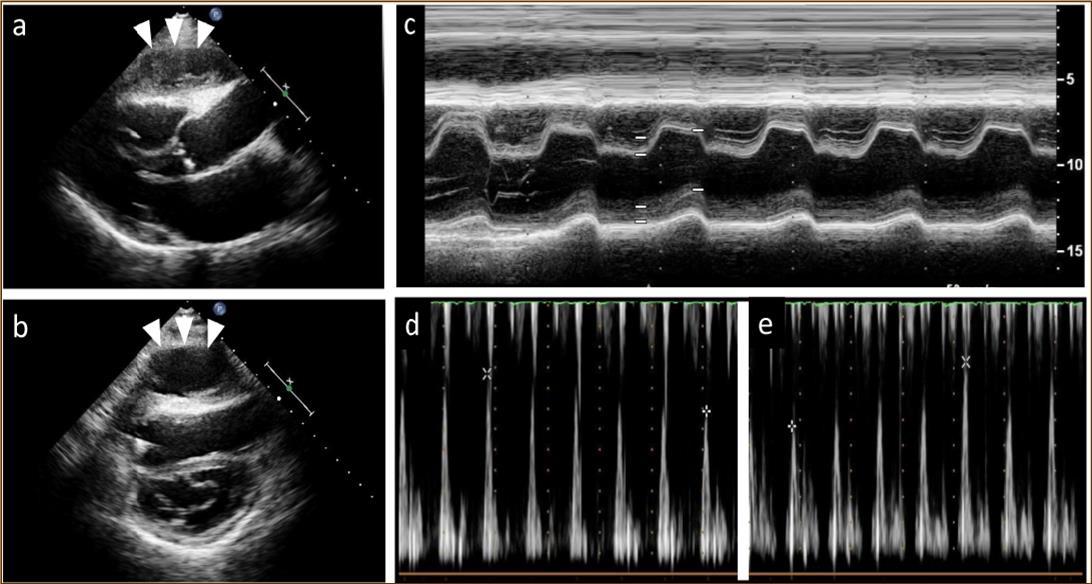

At 2 years post-HTx, when the patient first developed ACR, echocardiography revealed mild pericardial effusion, but there was no deterioration in hemodynamic parameters compared with the findings noted on previous examinations. ACR was considered as the cause of mild pericardial effusion and the dose of immunosuppressive regimens were increased. Two months after that, pericardial effusion persisted even though resolution of ACR was confirmed on EMB. At 2.5 years post-HTx, echocardiography revealed paradoxical septal motion and a large cystic-like mass with a thick capsule adhered to the right ventricle (Figure 1a, b). Roughly from that time, the patient began to experience dyspnea on mild exertion and lower leg edema. Oral diuretics were added to the prescription to relieve symptoms but dyspnea and edema did not resolve entirely.

Figure 1.Echocardiography findings. A large cystic-like mass with a thick capsule was found in front of the the right ventricle (white arrows) (a. long axis view; b. short axis view). Paradoxical septal motion were seen in a motion mode image of left ventricle (c). Respiratory variation in both mitral (d) and tricuspid inflow velocities (e) were seen.

At the age of 52 years, the patient was admitted to our institution for both evaluation of heart failure and regular right heart catheterization including EMB. With respect to allograft rejection, ACR was again detected on regular EMB, and the immunosuppressive regimens were strengthened. Further echocardiographic investigations were conducted to explore the implications of findings indicative of constrictive physiology with thickened pericardium. Respiratory variation in both mitral and tricuspid inflow velocities was seen, but these findings did not meet the complete criteria for CP diagnosis (Figure 1c-e). Magnetic resonance imaging of the heart revealed seroma and a thick cystic-like capsule tightly adhered to the right ventricle (Figure 2a, b). Right heart catheterization revealed elevation of right atrial pressure with severely reduced cardiac index (Figure 3a). The classic dip-and-plateau pattern of right ventricular diastolic pressure and equalization of right atrial pressure and right ventricular diastolic pressure were also observed (Figure 3b). Based on these results, effusive CP or cardiac tamponade-like hemodynamics were strongly suspected, although the etiology remained unknown. Therefore, at 3 years post-HTx, the patient initially underwent removal of the seroma through exploratory lateral thoracotomy to elucidate the etiology of the disease. Yellowish fluid was found and the fluid was completely aspirated. Immunosuppressive regimens including everolimus, which may interfere wound healing, were temporarily converted to standard three-drug regimens. Removal of the seroma via lateral thoracotomy did not lead to improvement in symptoms or hemodynamics. Pathological analysis revealed fibrin and seroma, but no malignant cells or infection. Since the initial procedure did not have any effect on the patient’s symptom, pericardiectomy through median sternotomy was performed at two months after the initial procedure. Intraoperative findings indicated a thickened pericardium and effusion in front of the right ventricle. At first, after sternotomy and adhesiotomy, the tissue in front of the right ventricle, which appeared to be thickened parietal pericardium, was completely resected and the effusion fluid was removed. However, high central venous pressure (20 mmHg) persisted, resulting in a displacement of the left ventricle by the right ventricle. Therefore, additional tissue from the front of the right ventricle was excised, corresponding to diffusely thickened visceral pericardium and epicardium. After the procedure, central venous pressure decreased from 20 to 10 mmHg, and displacement of left ventricle resolved. Pathological analysis of the resected tissues demonstrated chronic fibrosis and chronic inflammation with plasma cells, but no infectious etiology was identified (Figure 4 a, b). After the pericardiectomy, hemodynamics (Figure 3a, c) and symptoms improved, and the patient is currently experiencing a favorable clinical course without complications.